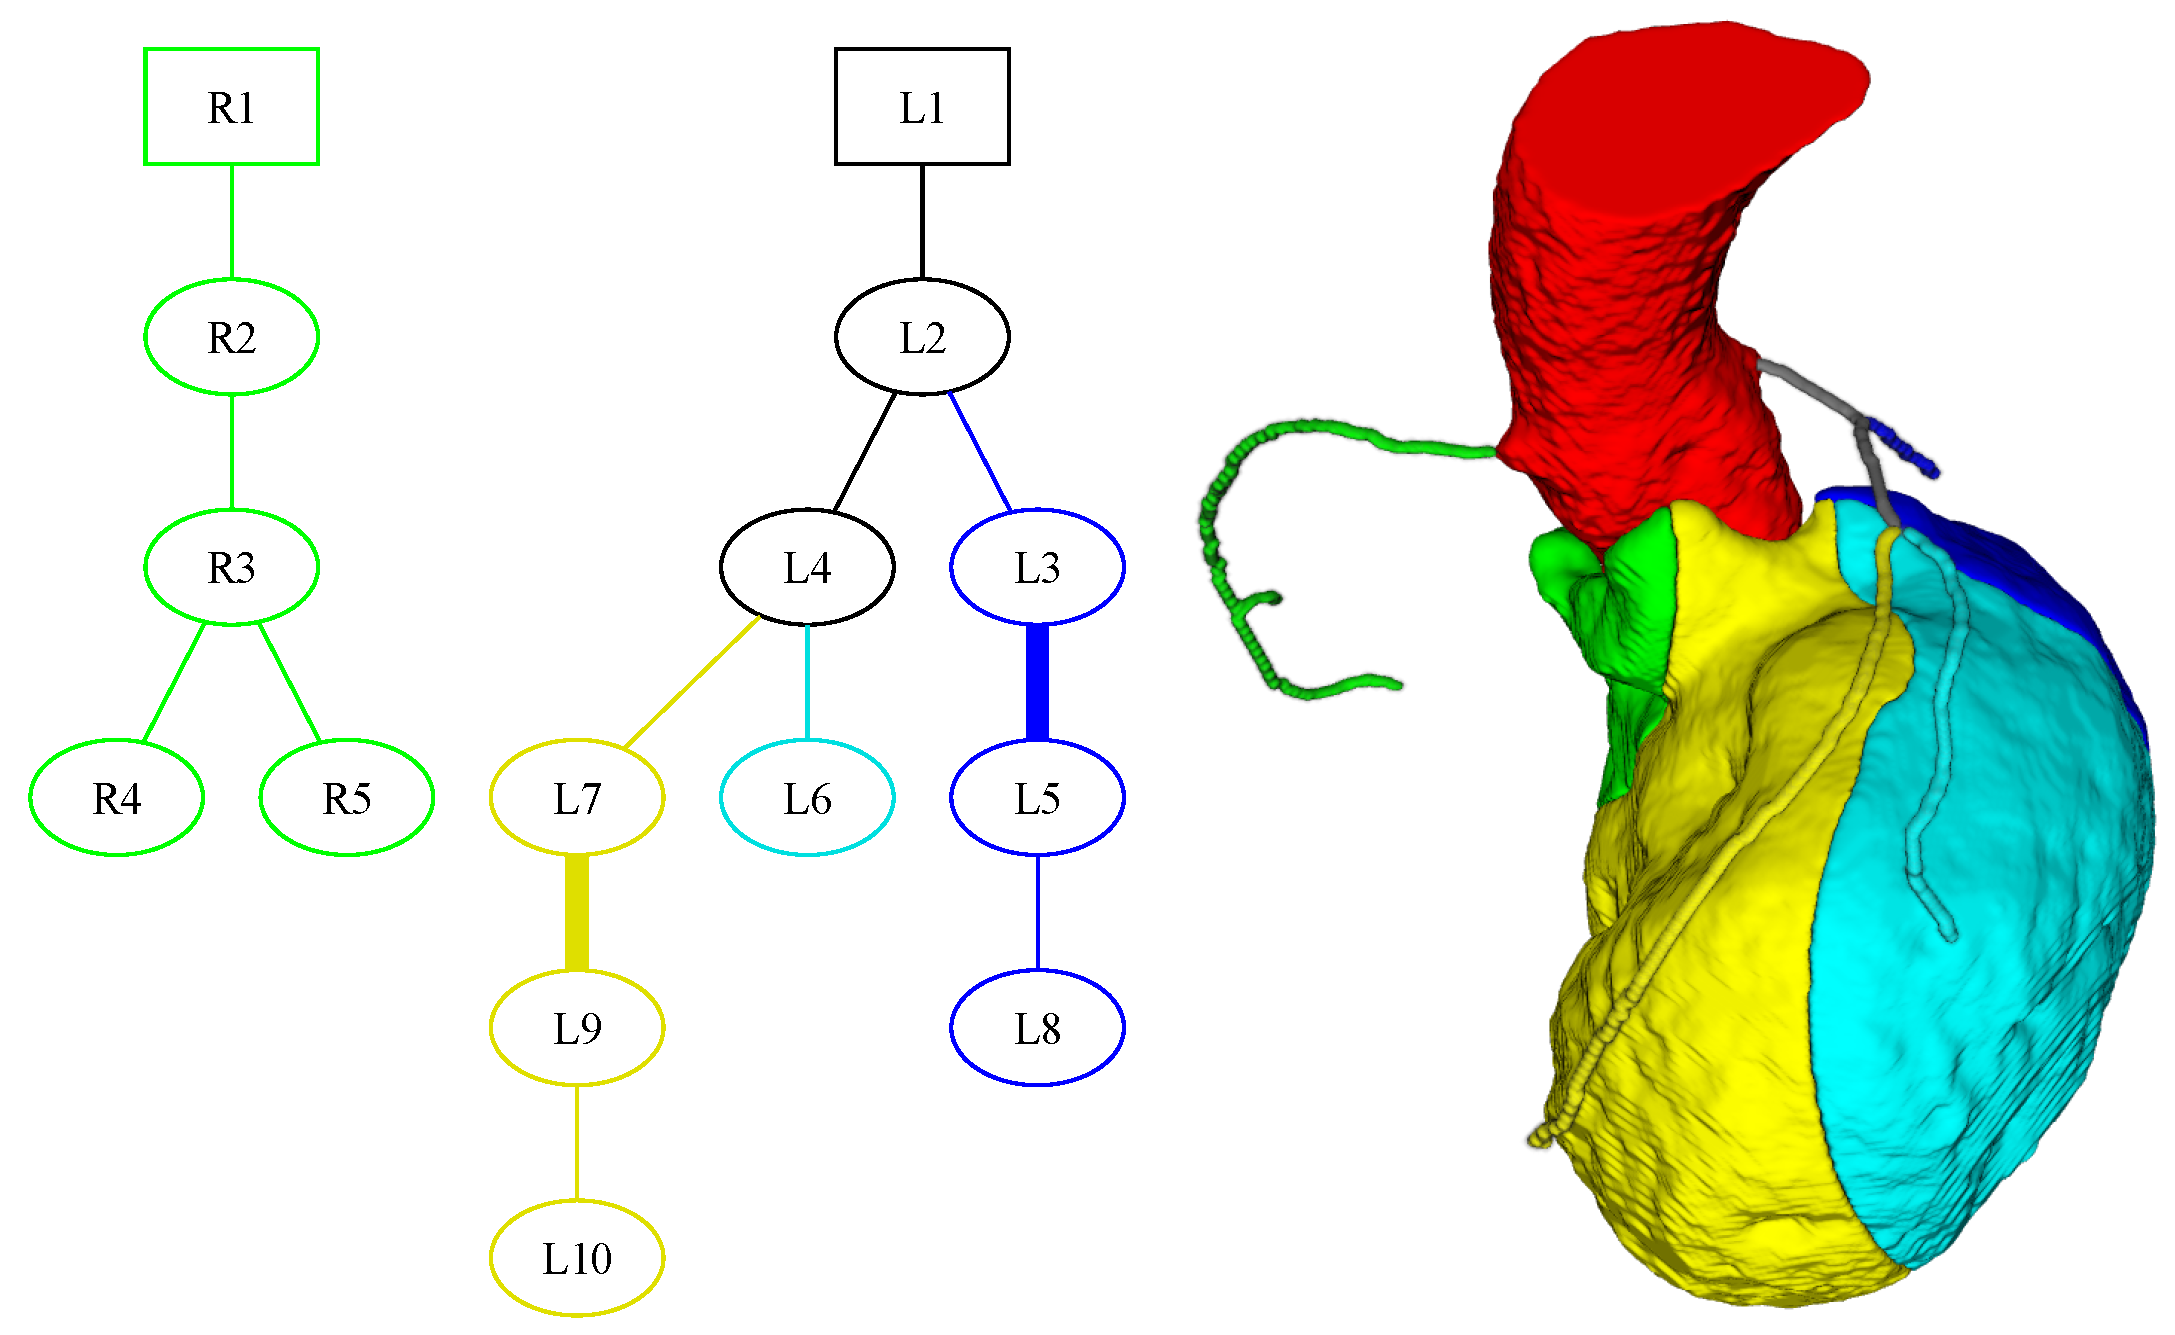

3. Segmentation and Partitioning of Coronary Vessels and Microcirculation